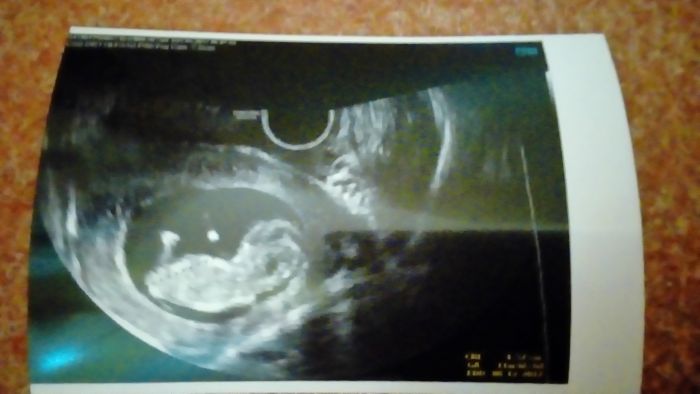

Ahoj holky, tak screening mám za sebou. Uf. Vše dopadlo dobře. Akorát ve 20.tt kromě velkého ultrazvuku musím na genetickou konzultaci kvůli tomu, že syn má vrozenou vadu srdce, která ani nemohla být screeningem odhalena, tak se budou více zaměřovat na srdeční vady. Koukala jsem na čísla a porovnávala je s výsledky před 2mi lety u syna a i ty 2 roky hodně výsledky změní a to jsem si říkala, že 2 roky to tolik neovlivní. Ale čísla jsou pořád krásná. Je mi 28 let a trizomie 21 mi vyšla s rizikem 1:15022, trizomie 18 s rizikem 1:35393 a trizomie 13 s rizikem 1:111374. Takže jsem spokojená. Vše se zdálo být v pořádku. Doktorka se nás ptala zda má zkoumat přesně o jaké pohlaví se jedná, tak jsme řekli, že to chceme jako překvapení, tak snad nám to tentokrát nikdo nevyzradí. Termín porodu mám mít 4.12. A dle screeningu jsem 12+1 a dle menstruace 12+0 takže už miminko není o týden mladší jak na začátku bylo. Manžel si ultravuk natáčel na kameru a doma jsme se kochali nad tou krásou :-)

[999767] krásné už to pěkně roste ty miminka